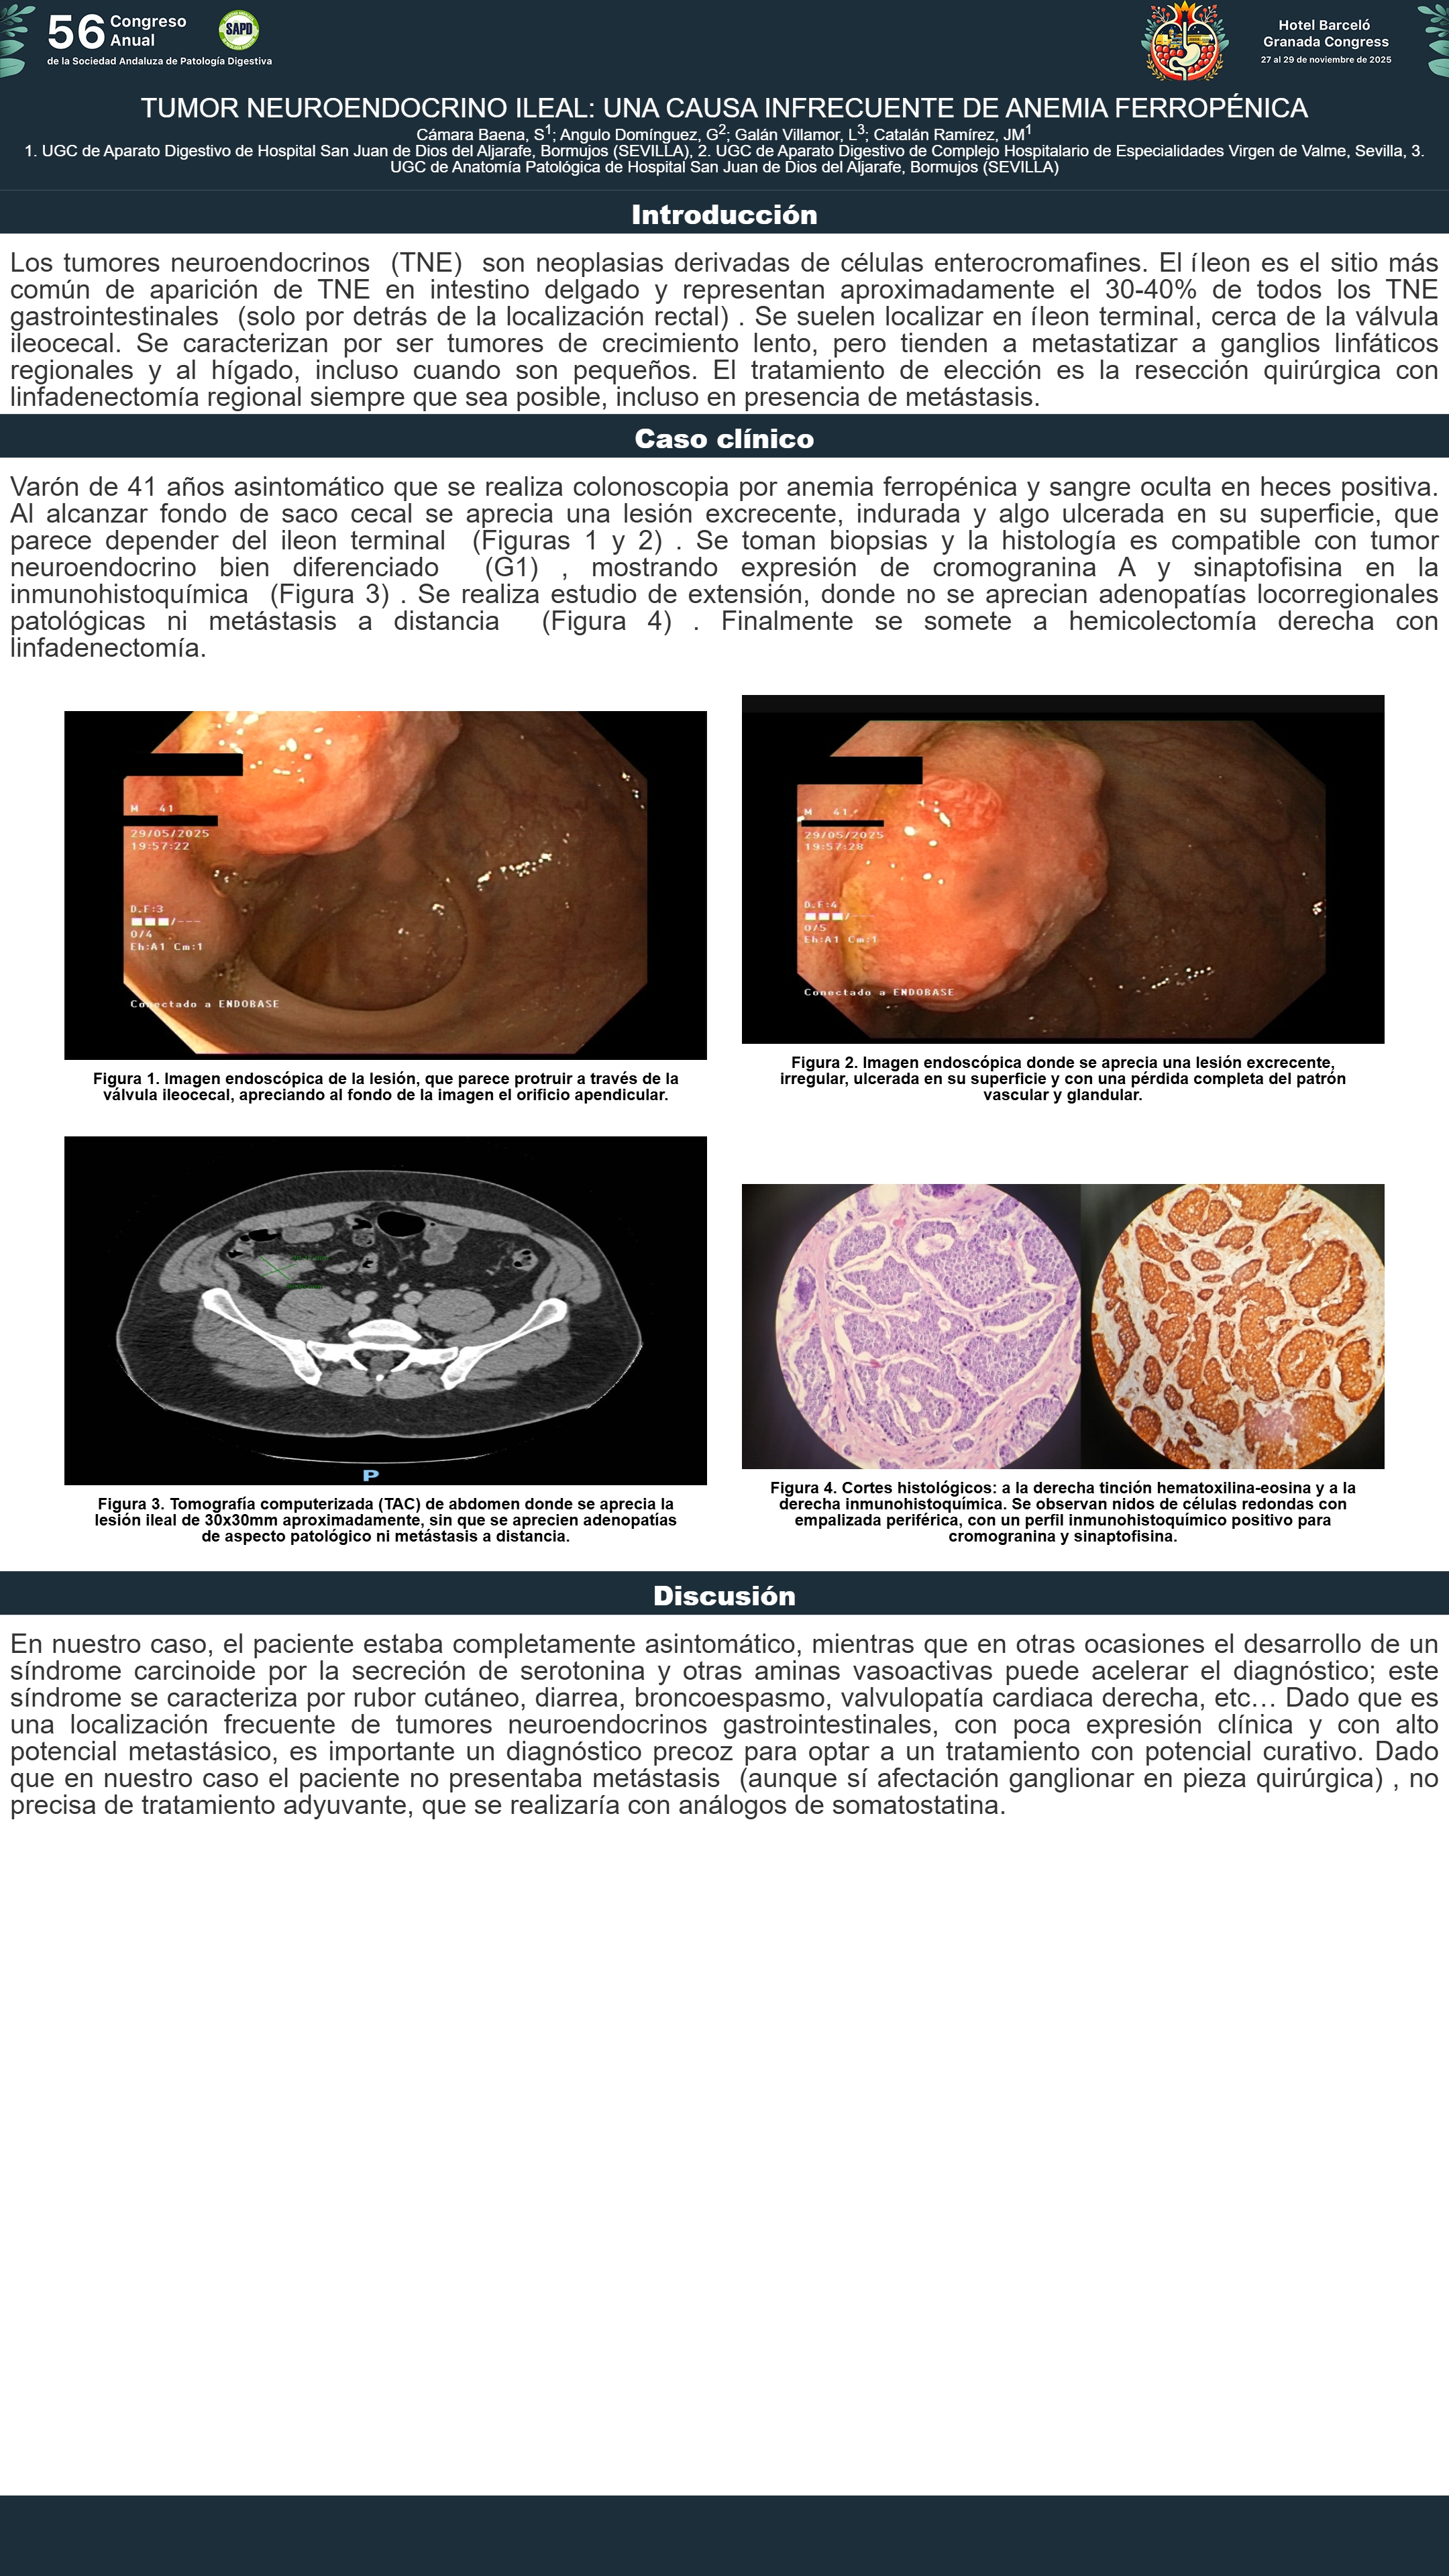

[CP-146] PANCREATITIS AGUDA GRAVE POR ANTIHIPERTENSIVOS, CAUSA INFRECUENTE A TENER EN CUENTA